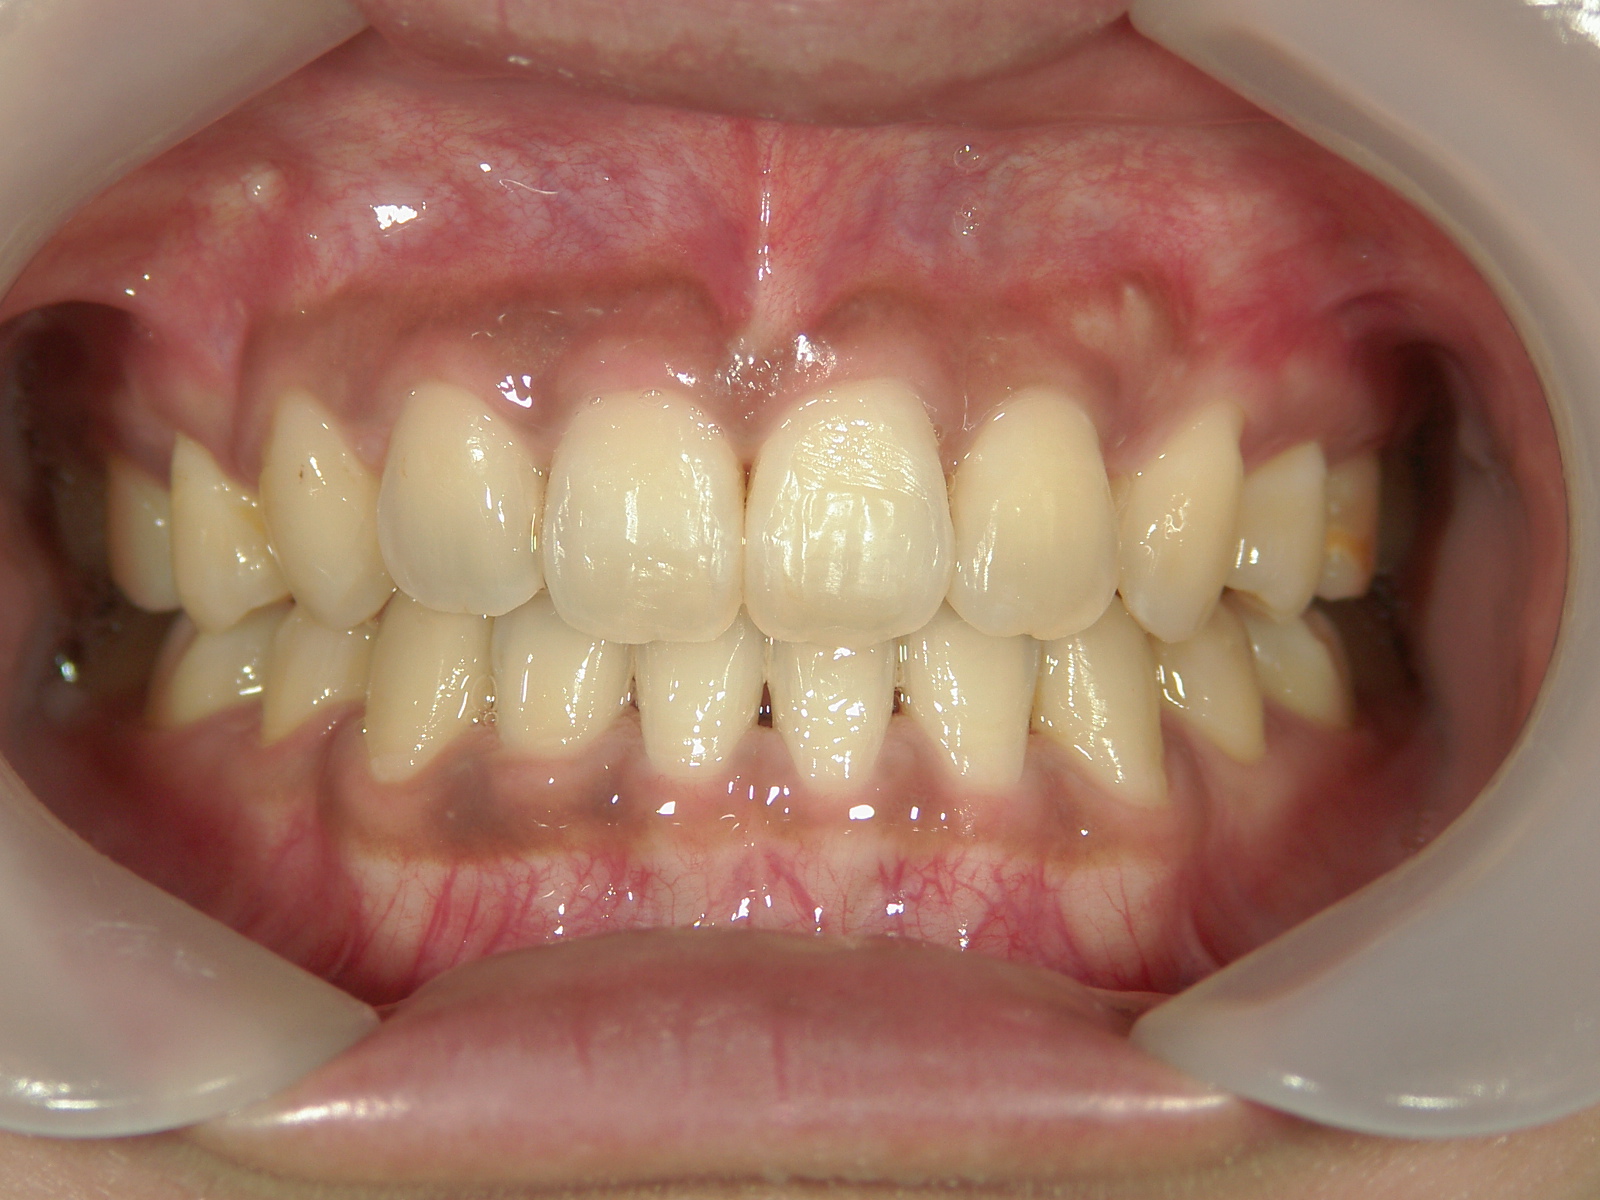

全顎ワイヤー矯正 症例(6)

主訴: 噛み合わせが悪い

②Ⅱ級ゴムを併用し、隙間を閉鎖しました。

③歯根を移動し、咬合を緊密化させました。

カテゴリー : ガタガタ(叢生) , 噛み合わせが深い(過蓋咬合)